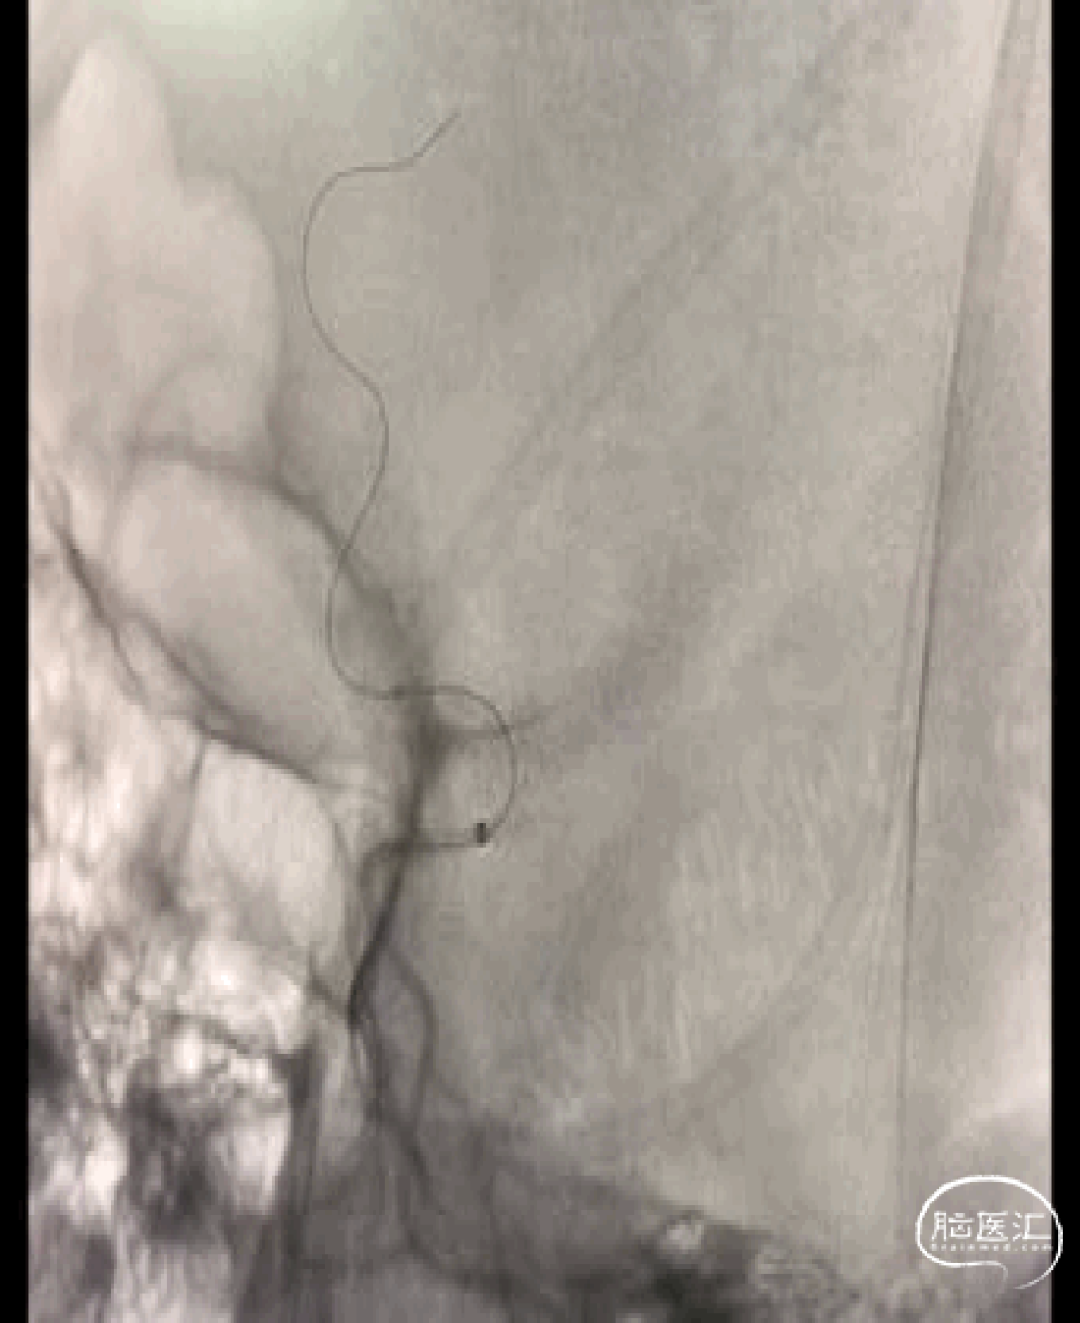

一例左侧大脑中动脉M3段闭塞远端

抽吸导管血管再通治疗

作者:高军、温昌明

视频动图如下: